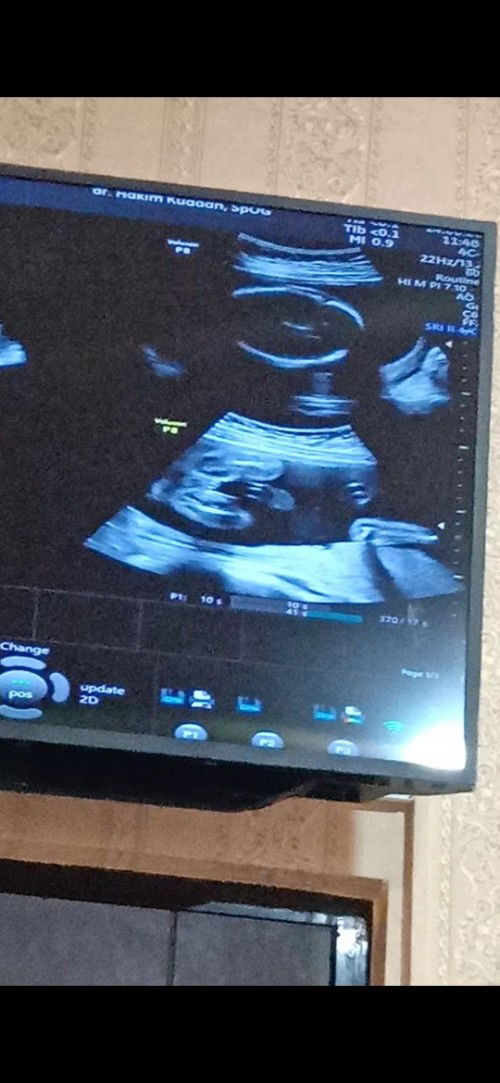

Assalamualaikum bunda, kata dokter JK laki2, menurut bunda2 ini sudah jelas laki2 atau Perempuan.

Baca lagism kyak aq dokter bilang jk ny cowok tebakan paksu bnr pl, malah gak ngerti kt dokter ni monas nya ๐คญ kt paksu anak cowo itu cnta pertma nya sm mama nya jagain bnget mama nya, dia gak mau mama nya ad apa2 jd dia care bnget sm mama nya, aq sneng aja bun krn aq gak mmpermslahkan jk asal anak shat, gak krg apa pun n smua nrmal dh lega bun hati ini sbgai mamakk apa lagi ini jg anak pertma stelah 7 taon stelah 2 taon isi ternyta bo bun

sebelumnya trimakasih sudah memberi tanggapan ya bunda, usia kandungan sudah 27minggu, karna belajar dri sodara dulu pas di usg cowok ternyata yg keluar cewek, semua perlengkapan sudah di siapkan cowok, ini untuk mawas diri aja bunda, karna ini bru kehamilan pertama saya, terimakasih sarannya bunda2 semua, semoga sehat selalu

kalo menurut USG kelihatan banget laki laki ya bund.Tapi mending nyiapin bajunya yang netral tetangga sebelah rumah saya baru saja melahirkan kemarin selasa setiap di USG cowo,monasnya juga kelihatan di hasil USG karena saya lihat.Eh kemarin pas lahir cewe.Mau heran tp nyata

ini hasil usg ku bun..dokter blg jk debay cwo..yg aku lingkari biru itu monas/bkn yah?mudah2an aja bnr ps lahir cwo bun tp aku bli baju2nya kebanyakan gambar hewan sih jadi bs dipake baby boy or girl๐

Sepertinya sudah jelas itu cowo ya bun, tp kembali lagi ini penglihatan awam yaa, kalo belum yakin baiknya bulan depan bisa USG lagi dengan USG 4D agar lebih jelas dan meyakinkan